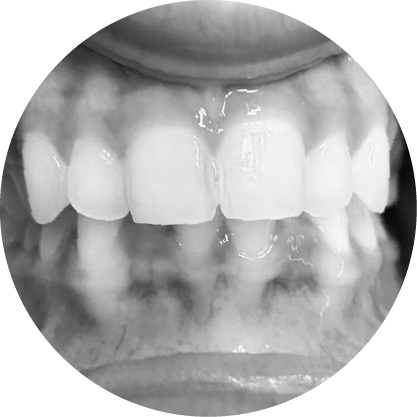

ช่องว่างระหว่างฟัน (Diastema)

การปิดช่องว่างระหว่างฟัน เพื่อรอยยิ้มที่สมบูรณ์แบบ

"ช่องว่างระหว่างฟันหรือไดแอสเทมา หมายถึงช่องว่างระหว่างฟันที่เห็นได้ชัด ซึ่งอาจเป็นปัญหาทางความงามสำหรับหลายๆ คนการจัดฟันสามารถปิดช่องว่าง เหล่านี้ได้อย่างมีประสิทธิภาพทำให้มีรอยยิ้มที่สม่ำเสมอและสวยงาม"

ตัวอย่างในชีวิตจริง